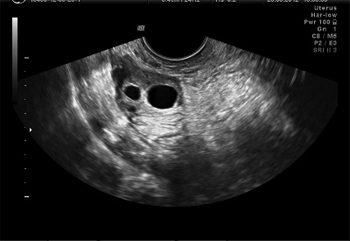

При I типе эхографической структуры, выявля-емом у 25,5% (12) больных с аутоиммунным оофо- ритом, яичники определялись как гомогенные сим-метричные образования повышенной эхогенности. Определялись жидкостные включения размером от точечных до округлых (в среднем диаметр составлял 0,3см), рассеянные по всей строме яичников (антральные фолликулы). При автоматическом определении количества антральных фолликулов AFC (antral follicle count) нормальный или высокий – 11–17. При динамическом наблюдении отмечались периоды изменения эхогенности внутренних участков яичников, однако повышение звукопроводимости в связи с ростом отдельных фолликулов на эхограммах отчетливо не выявлялось (рис.1). Описанные эхографические параметры яичников, которые регистрировались на протяжение всего периода мониторинга, рассматриваются как проявление мелкокистозной дегенерации незрелых фолликулов и выявляются у всех больных с АО с опсоолигоменореей и аменореей (первичной и вторичной).

Рис. 1. I тип эхограммы яичников и ее схематическое изображение Мелкокистозная дегенерация незрелых фолликулов, регистрируемая на протяжении всего периода мониторинга.